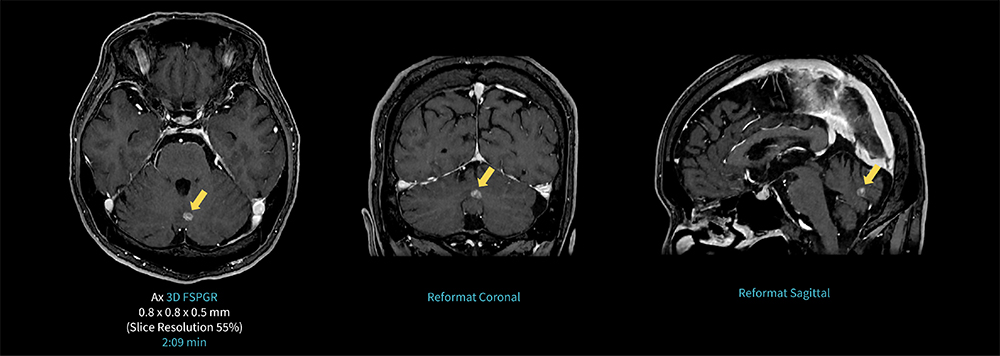

Case1 3D FSPGR/脳転移に対する定位放射線治療後の経過観察

60代、男性。脳転移に対して放射線治療後のフォローアップで造影MRI検査を施行した。

右前頭葉に14㎜大、左後頭葉内側に5㎜大、小脳虫部に7㎜大のGd増強効果を呈する結節を認めるが、前回との比較により増強効果は減弱しており、定位照射の治療効果が認められる。

AIR Recon DLを併用した3D FSPGRを2分程で撮像し、任意断面での観察が可能となる。

図1 3D FSPGR を用いた脳転移に対する定位放射線治療後の経過観察